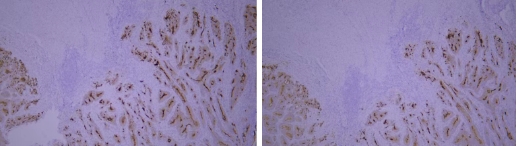

(VIII) Issues Related to Tissue-Specific Differences

Common problem: Staining results are inconsistent with expectations, showing negative or weak positive detection.

HER-2 staining results vary among different breast cancer samples.

Recommendation for Resolution: Set up positive tissue section controls. Due to significant differences in the expression of the same protein among different tissues, controls can help exclude the influence of the tissues themselves.